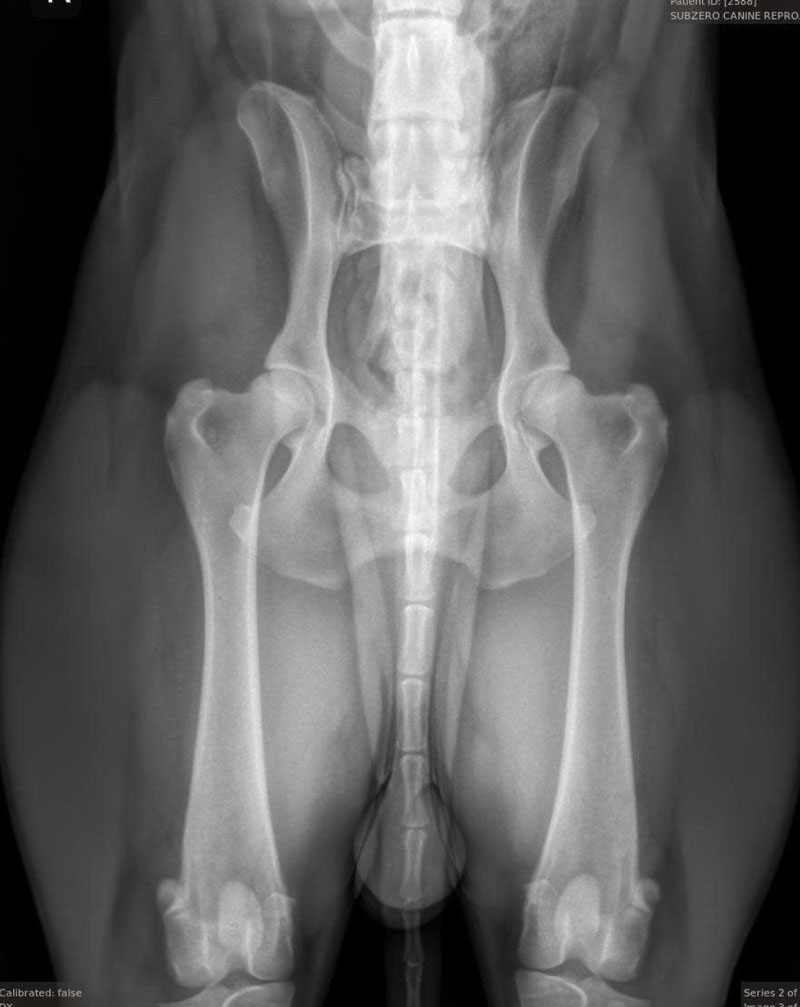

We are also proud to offer OFA (Orthopedic Foundation for Animals) image submissions. This is a requirement amongst many AKC breed clubs and may include several different image types such as:

We frequently receive inquiries regarding our success with proper positioning for OFA images, specifically for hips. Translating this success can be challenging, so we have included images of various breeds that we have taken. We take great pride in our success with these images and many others like them. As extreme perfectionists, we appreciate owners who understand that we strive for the best technique and outcome while minimizing stress and ensuring the comfort of your dog(s), particularly since all images taken here are done WITHOUT sedation.